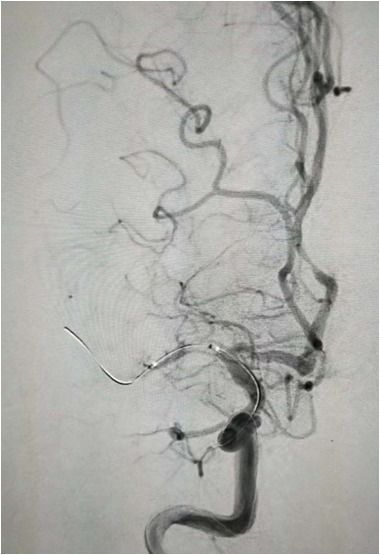

导丝导管通过闭塞部位,经微导管造影,证实在远端真腔内,取栓后M1重度狭窄,球囊扩张。

球囊扩张

支架植入术后前向血流通畅

右侧椎动脉造影:基底动脉中段充盈缺损,基底动脉尖丢失。提示基底动脉中段原位狭窄基础上血栓形成,血栓脱落栓塞基底尖。

微导丝微导管通过闭塞部位,经微导管造影,确认在远端真腔。

一把拉通后,前向血流即刻恢复至3级,双侧小脑上动脉、大脑后动脉、基底动脉尖显影。